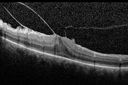

Vitreomacular traction - spontaneous release left eye

VMT-2013-2019_masmi.jpg

1 files, last one added on Aug 07, 2019

Album viewed 349 times